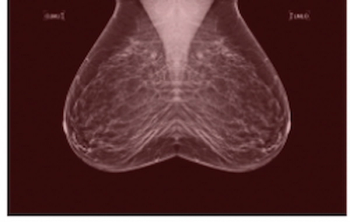

Reportedly the first randomized trial to examine the impact of artificial intelligence (AI) on screening mammography, researchers found AI-aided screening led to a 20 percent increase in breast cancer detection and a 44.3 percent decrease in mammography screening workload.

In a dataset enriched for African American women, BRCA mutation carriers and those with benign breast disease, a mammography-based deep learning model demonstrated a five-year AUC of 63 percent for predicting breast cancer in comparison to 54 percent for BI-RADS assessment.

Ultravist is reportedly the first contrast agent to gain a specific indication for visualization of known or suspected lesions on contrast-enhanced mammography, which was recently recommended by the American College of Radiology as a supplemental imaging alternative to magnetic resonance imaging (MRI) in women with dense breasts at the age of 40 and other risk factors for breast cancer.